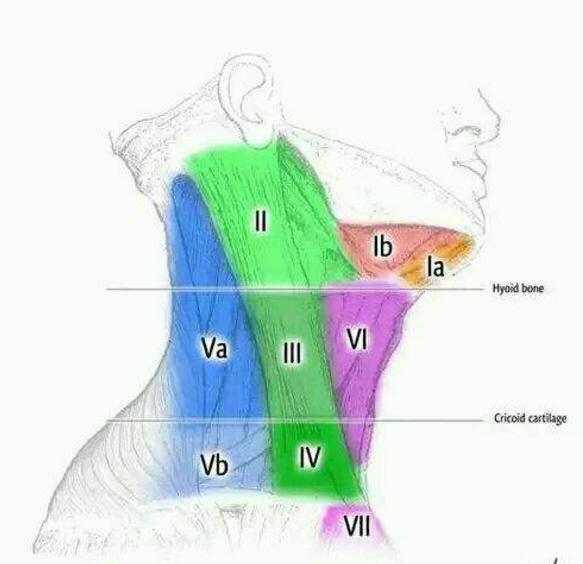

三大奇葩说甲状腺癌的淋巴结转移 – 知乎

颈部淋巴结转移性鳞癌,原发肿瘤究竟在哪里?_药智论坛

喉癌并颈部淋巴结转移